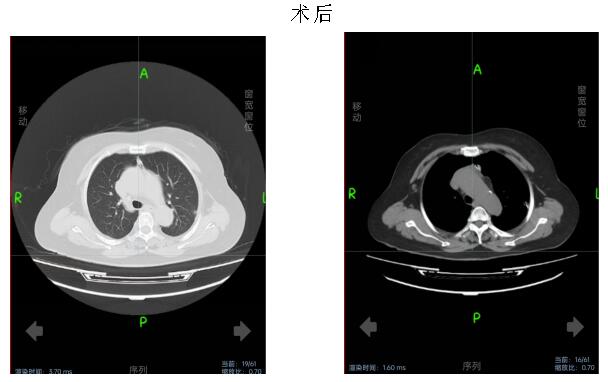

患者女性,70岁,体检发现前纵隔占位性病变遂就诊于市中心医院。入院后完善术前检查,排除手术禁忌症,经胸外科杨斌主任医师、副主任医师李卫国、主治医师车小川讨论病情,并向患者讲明病情并征求患者及家属同意后,积极完善术前准备。

术中,在麻醉手术科配合下,李卫国带领胸外科团队为患者行胸腔镜经剑突肋缘三孔式胸腺病损切除术。术中送冰冻,30分钟后病理报告提示胸腺瘤,术后生命体征平稳,给予镇静止痛、营养支持等对症治疗。术后第3天复查胸部CT未见明显积液积气。患者无特殊不适。